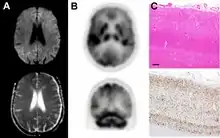

MRI of iCJD because of growth hormone

The defective protein can be transmitted by contaminated harvested human brain products, corneal grafts,[23] dural grafts,[24] or electrode[25] implants and human growth hormone.[26]

dwMRI, FDG PET and post mortem histology from a patient who presented with sCJD aged 66

Brain FDG PET-CT tends to be markedly abnormal, and is increasingly used in the investigation of dementias.

• Patients with CJD will normally have hypometabolism on FDG PET.[50]

Histopathology

Spongiform change in CJD

Testing of tissue remains the most definitive way of confirming the diagnosis of CJD, although it must be recognized that even biopsy is not always conclusive.[51]

In one-third of people with sporadic CJD, deposits of "prion protein (scrapie)", PrPSc, can be found in the skeletal muscle and/or the spleen.[52] Diagnosis of vCJD can be supported by biopsy of the tonsils, which harbor significant amounts of PrPSc; however, biopsy of brain tissue is the definitive diagnostic test for all other forms of prion disease. Due to its invasiveness, biopsy will not be done if clinical suspicion is sufficiently high or low. A negative biopsy does not rule out CJD, since it may predominate in a specific part of the brain.[53]

The classic histologic appearance is spongiform change in the gray matter: the presence of many round vacuoles from one to 50 micrometers in the neuropil, in all six cortical layers in the cerebral cortex or with diffuse involvement of the cerebellar molecular layer.[54] These vacuoles appear glassy or eosinophilic and may coalesce. Neuronal loss and gliosis are also seen.[55] Plaques of amyloid-like material can be seen in the neocortex in some cases of CJD.[56]